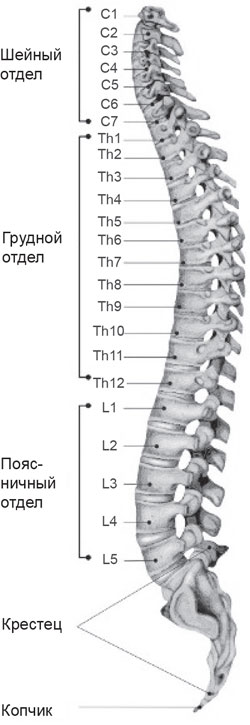

Позвонок Th10: анатомия и фото медицинских иллюстраций